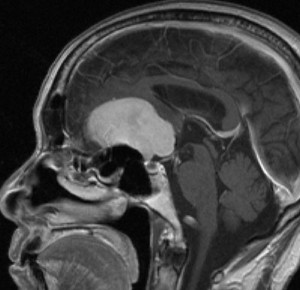

大後頭孔(大孔)髄膜腫 foramen magnum meningioma)

この腫瘍はfarlateral approachなどの頭蓋底手術をしなくても,外側後頭窩開頭で全摘出できます。要領は,S状静脈洞の下端の周囲骨を削除することです。大後頭孔髄膜種は延髄を圧迫するので巨大なものはありません。出血のコントロールや延髄からの剥離は比較的容易なものが多いでしょう。舌咽神経と迷走神経損傷を避けることが重点となります。

迷走神経と舌咽神経は機能温存できました。舌下神経が腫瘍の表面に薄く広がり剥がすことができずに半分以上を切断しています。でも片側舌下神経麻痺では日常生活に困ることはあまりありません。